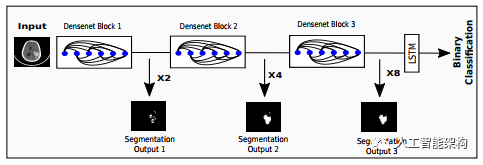

我们决定将建立序列建模,其中序列的每个元素都是2D切片,其中有也包含不是感兴趣的区域。卷积神经网络对每个图像进行建模,其中标记的感兴趣区域用作分类标签,并且来自这种DenseNet的整个序列的表示通过双向LSTM传递到模型上下文。循环(LSTM)模型与DenseNets的关注,我们称之为RADNet。